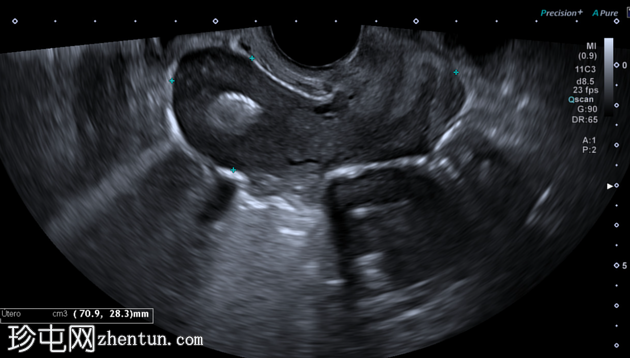

2.png

矢状切面

纵切面和横切面经阴道超声图像显示子宫内膜腔内有一个高回声肿块,呈圆形,并具有典型的“珍珠串”样外观,符合宫内节育器(IUB)的特征。

在超声图像上,宫内节育器通常表现为子宫内膜腔内的高回声圆形结构,常呈现出由铜线圈产生的典型“珍珠串”样外观。在高分辨率经阴道超声检查中,纵切面和横切面均可清晰显示该特征。后方声影可能存在,但通常不如硬性宫内节育器(IUD)的后方声影明显。